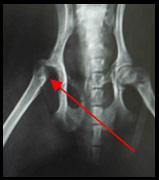

Fracture du col fémoral

Votre animal s’est fracturé l’os de la cuisse à l’endroit où celui-ci s’articule avec le bassin. Un plâtre n’a pu être mis en place pour stabiliser la fracture parce qu’il est impossible d’immobiliser la hanche. Nous avons donc dû retirer chirurgicalement le morceau de fémur qui était encore attaché à la hanche.